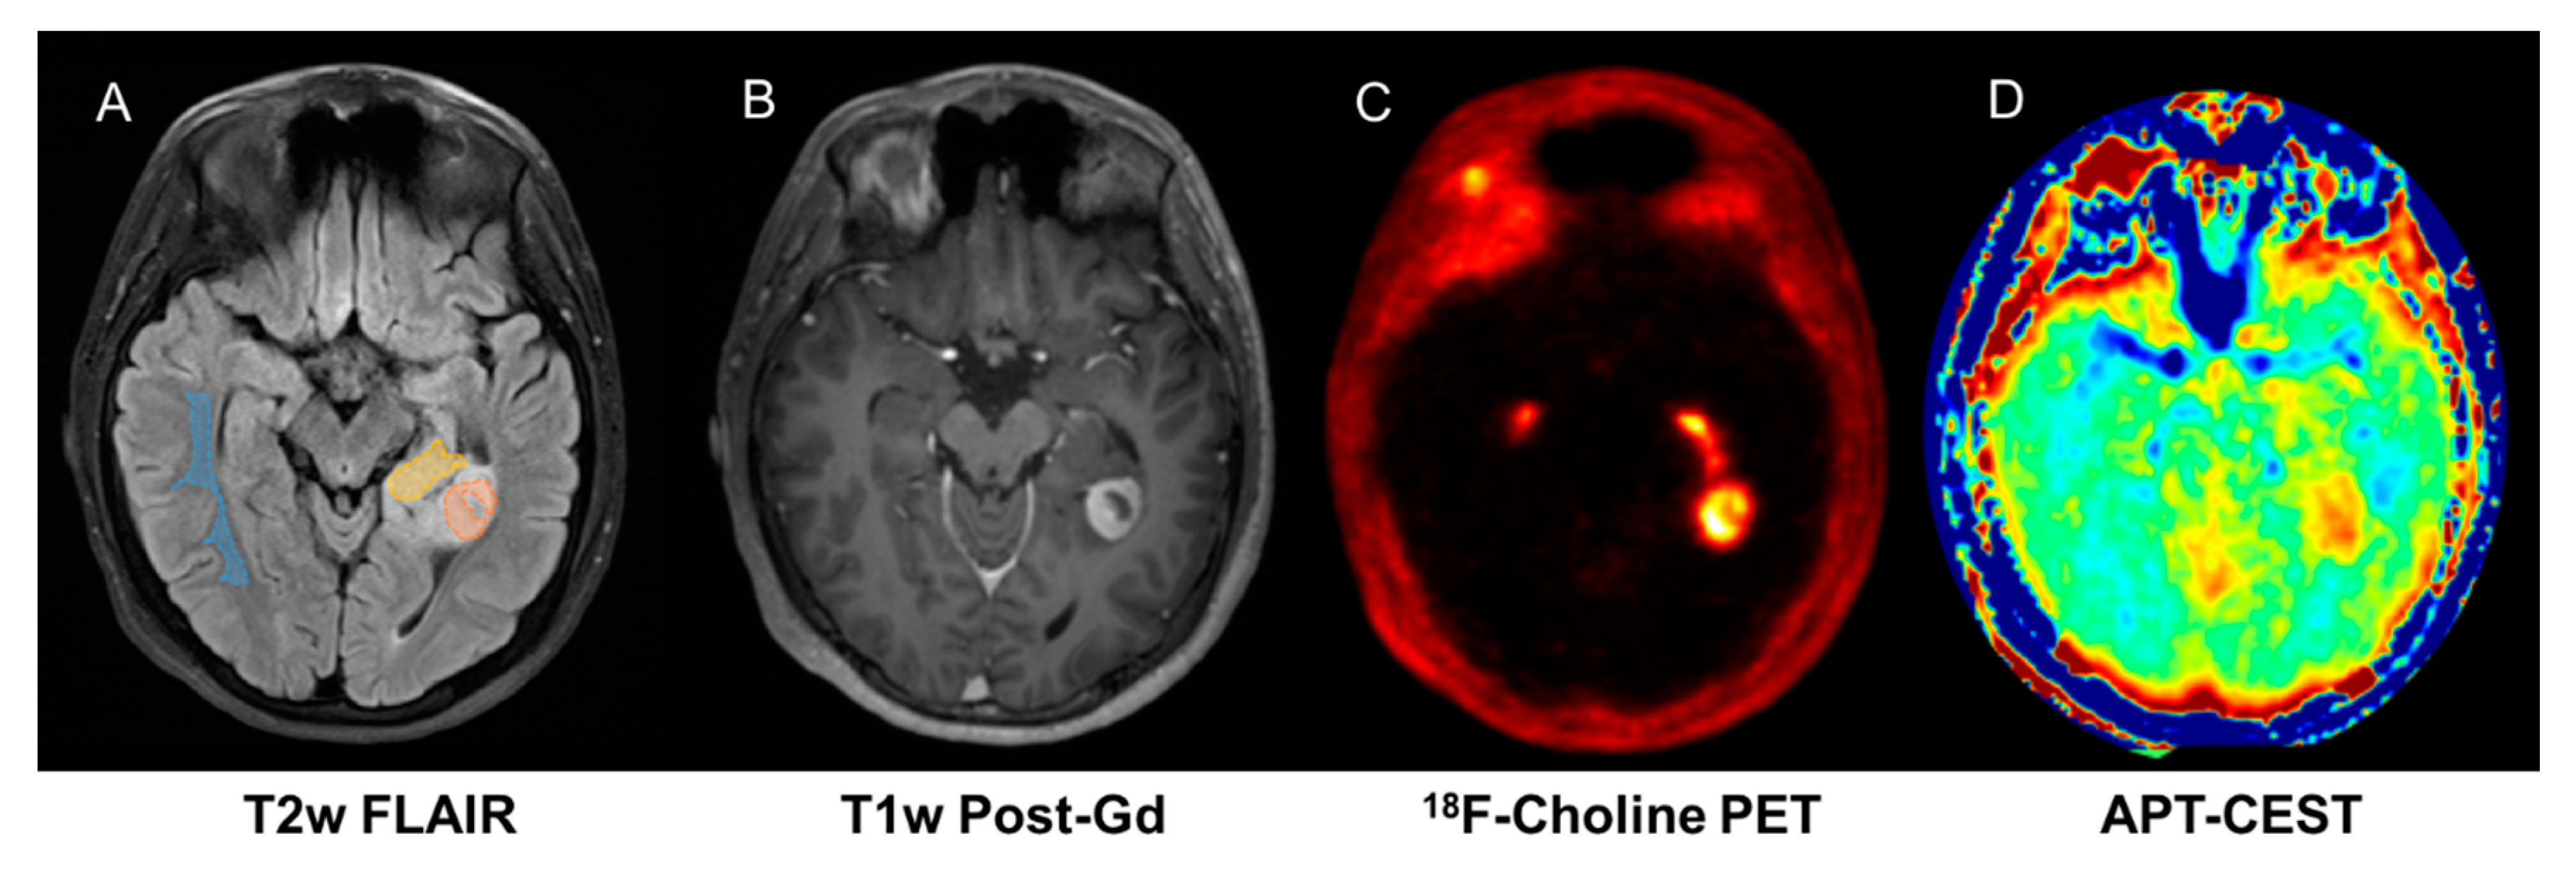

Although combining PET imaging with advanced MRI provides an opportunity to improve overall diagnostic accuracy in neuro-oncology, to date, very few published studies have investigated this potential, mainly focussing on feasibility or agreement of modalities [13,15]. In paediatric neuro-oncology, the literature is even more scarce, limited to case reports and small feasibility studies, but the prevailing literature does support a role for amino acid PET [20]. We have previously shown that 18F-choline PET–MRI improves response assessment in treated gliomas [17,30] and can be used to validate novel MRI techniques such as Amide Proton Transfer-Chemical Exchange Saturation Transfer (APT-CEST) [18] (Figure 3). In addition, we have shown that 18FDOPA PET–MRI improves assessment of post-treatment glioma burden compared to MRI alone [61].

Figure 3.

Fifteen-year-old male with pilocytic astrocytoma imaged on hybrid PET/MR which enables exact co-registration of FCho (C) with APT-CEST (D) showing correlation in enhancing ((B), T1 contrast) and non-enhancing tumour components. ((A), T2 FLAIR).